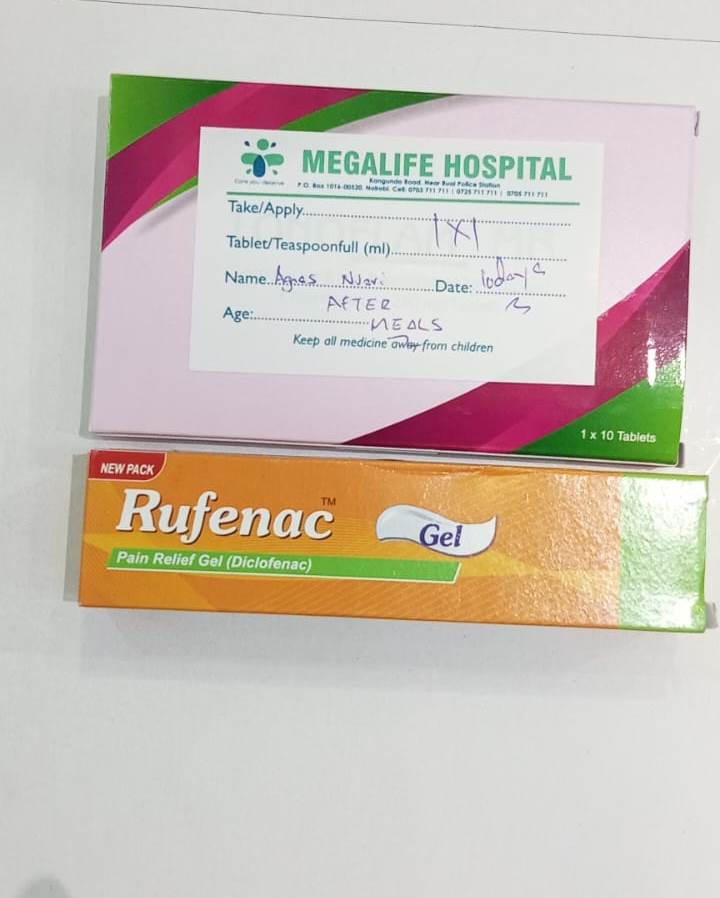

Comprehensive healthcare ensuring every child's physical well-being through preventive care, treatment, and health education. Our program provides 24/7 medical access through partnerships with leading hospitals in Nairobi.

Our Healthcare & Medical Services program is built on the belief that every child deserves access to quality healthcare. Recognizing that health is fundamental to a child's development, we provide comprehensive medical care that addresses both physical and preventive health needs.

Established in 2005 in response to the critical healthcare needs of vulnerable children in our care, this program has grown to include partnerships with five major hospitals in Nairobi. We provide regular medical checkups, complete vaccination schedules, dental care, emergency treatment, and specialized care when needed.

24/7 Emergency Care

Round-the-clock access to emergency medical services through hospital partnerships, ensuring immediate care for accidents and sudden illnesses.

Medications & Vaccines

Routine medications, emergency drugs, vaccines